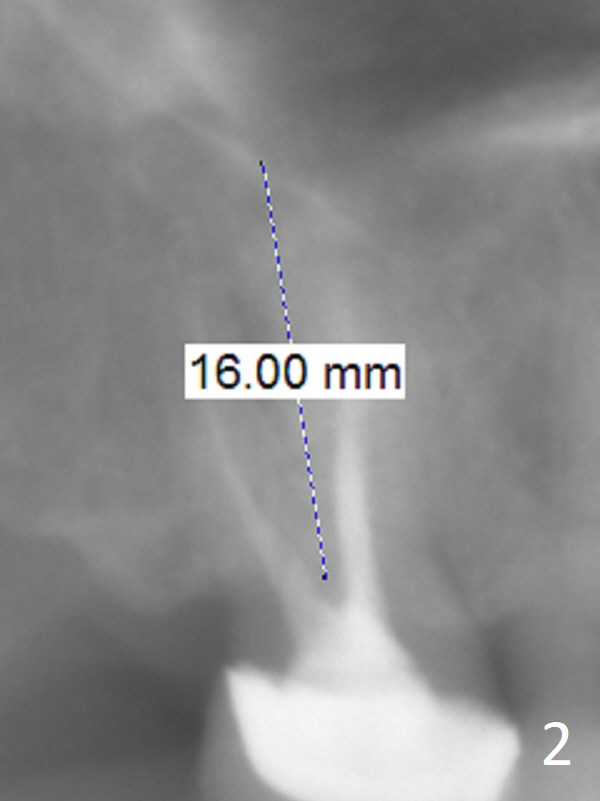

A 58-year-old woman has had RCT done at #2 for several years. The roots are trifurcated with sufficient bone height (Fig.1-3). Recently the tooth becomes symptomatic with formation of a distal fistula (Fig.4). After extraction, the septum (Fig.5 S) may be wide enough for initial drill (Fig.6). If not, resection the thin part of the septum (Fig.7 red line, with small or medium Rongeur) and use the initial drill (Fig.8). Anyway, take PA immediately to avoid sinus membrane perforation. If possible, adopt single drill technique.